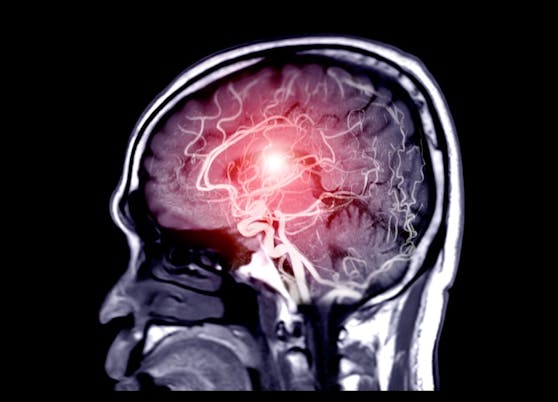

Der SARS-CoV-2-Erreger dringt bei einer Infektion auch ins Gehirn vor. Nun gibt es neue Erkenntnisse, was es dort bewirkt.

Aber der Corona-Erreger kann weit mehr anrichten, als verschwommenes Denken. Das Long Covid-Syndrom umfasst Beschwerden wie Kopfschmerzen, Angstzuständen, Depressionen, Halluzinationen und lebhaften Träumen bis hin zu den bekannten Geruchs- und Geschmacksanomalien. Eine Studie ergab, dass es bei mehr als 80 Prozent der untersuchten Corona-Patienten zu neurologischen Komplikationen kam. Alles Beschwerden, die im Gehirn verursacht werden. Wie das Virus die Blut-Hirn-Schranke überwindet und anschließend Nervenzellen infiziert, ist Gegenstand eifriger Forschung.

Die Blut-Hirn-Schranke ist die Grenze zwischen Blut und Zentralnervensystem. Durch die Zellen, die der Gefäßwand außen anliegen, können nur bestimmte Stoffe ins Gehirn übertreten. Dadurch wird das Gehirn vor schädlichen Stoffen, Krankheitserregern und Giften geschützt. Allerdings schaffen es manche Erreger, wie das Coronavirus oder auch Coxsackie-, Polio-, Varizellen-, Epstein-Barr- und Adenoviren in Gehirnzellen einzudringen.